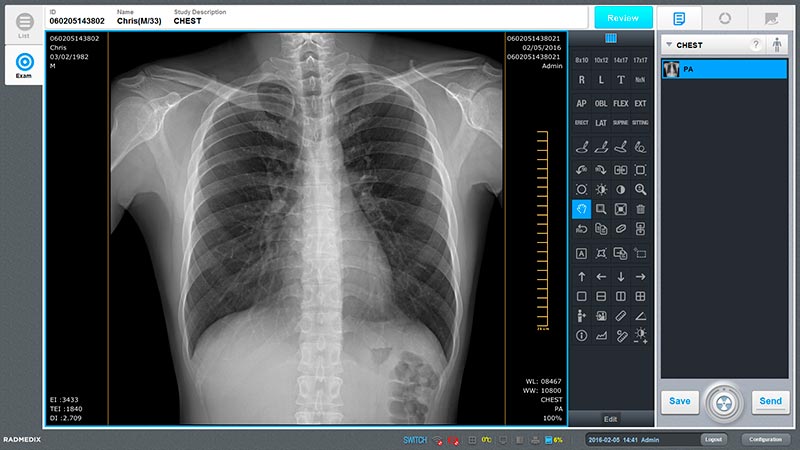

Radiología General

Adaptados a cualquier práctica, equipe su sala con herramientas modernas y de uso intuitivo haciendo el trabajo más fácil a sus profesionales.